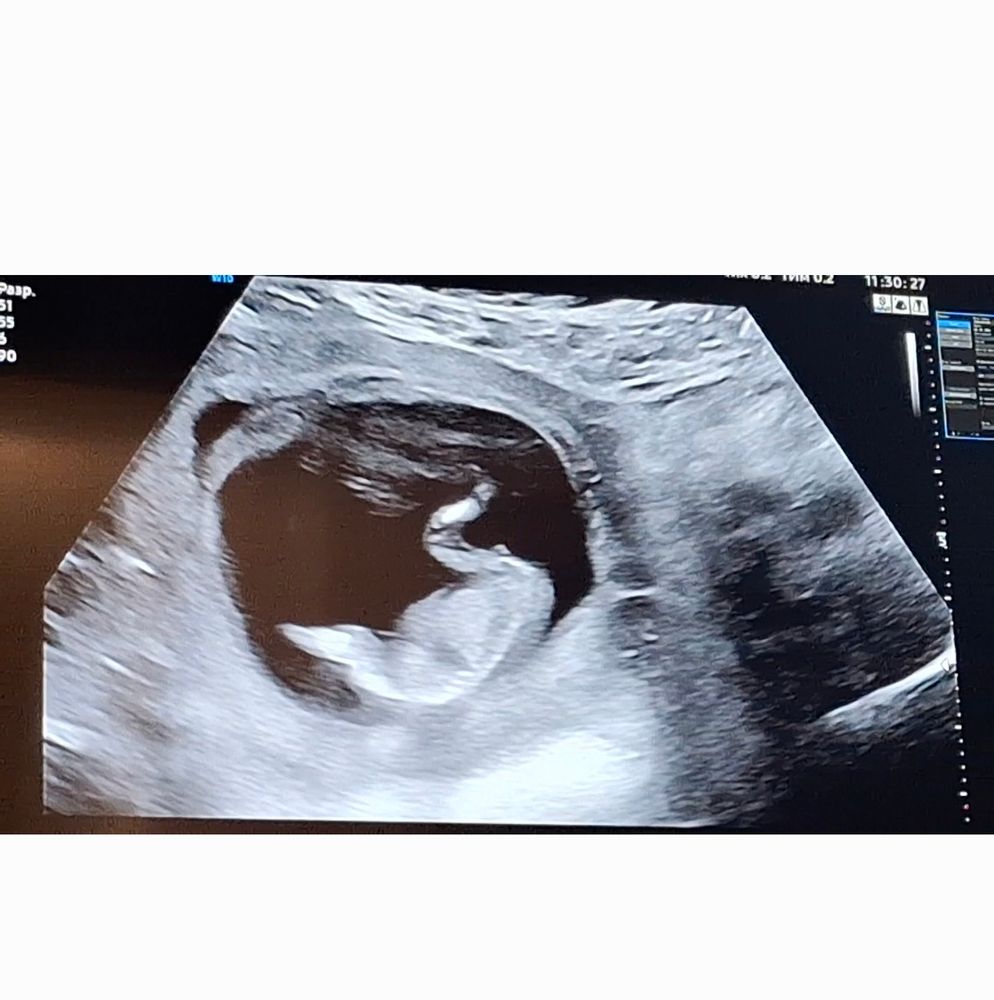

15 недель))пол малыша❤️

Вчера была на узи.14.5 недель по размерам малыша.14.6 по месячным.Сразу сказала,что мальчик.Показала на экране,жаль не сфоткала.В инете нашла фото,в точности,как наше .Я засмеялась,когда сказали пол,от радости,конечно))не расстраиваться же из-за такого,когда все со здоровьем в порядке Альхьамдулиллах1 ❤️Я спросила,точно ли это. Она меня и туда,и сбда вертела, смотрела со всех ракурсов.Потом попросила резко перевернуться с боку на спину.Та же картина😂я и сама видела все,без слов))не в первый раз,как говорится.С младшим она же ровно в 12 недель сказала правильно))Как думаете,уже можно настраиваться быть мамочкой ещё одного сыночка?))Фото с инета прилагаю.Есди что,я рада и спрашиваю не в надежде,что ошиблись))Просто интересно мнение со стороны.на спину.Та же картина😂я и сама видела все,без слов))не в первый раз,как говорится.С младшим она же ровно в 12 недель сказала правильно))Как думаете,уже можно настраиваться быть мамочкой ещё одного сыночка?))Фото с инета прилагаю.Есди что,я рада и спрашиваю не в надежде,что ошиблись))Просто интересно мнение со стороны.